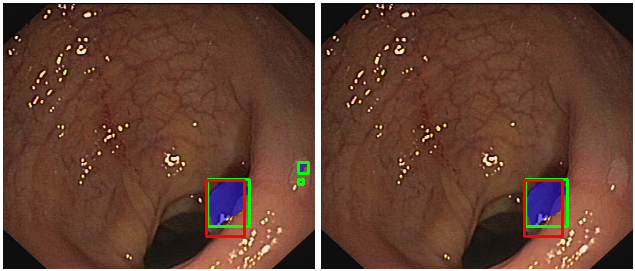

Accurate computer-aided colorectal polyp detection is a challenging problem since (i) colorectal polyps vary greatly in size, orientation, color, and texture and (ii) many polyps do not stand out from surrounding mucosa. As a result, some colorectal polyps are difficult to be detected. Figure 1 shows a few examples to illustrate these challenges. Previous polyp detection methods adopt hand-crafted features such as texture, color or shape and pass them to a detection framework to find the position of polyps [4, 5, 6]. However, these methods are not effective enough to be used in realistic clinical practice. Recently, with the renaissance of deep learning, the CNN-based deep neural network architecture has been widely used and proven to be a powerful approach for colorectal polyp detection and segmentation. Some studies used object detection methods, such as Faster R-CNN [7] or YOLO [8] to find and indicate polyps with bounding boxes [9, 10]. While these object detection based methods show excellent performance on recall and precision, they can not localize the polyps accurately on the pixel level. Physicians still need to find the polyp boundaries in the proposed bounding box during colonoscopy to remove them. Therefore, the computer aided system for colorectal polyp segmentation has great clinical significance and can reduce the doctor’s workload and segmentation errors from doctor’s subjectivity.

In order to compare our results with object-detection-based methods, we draw the minimum bounding box for each connected component in both output segmentation map and ground truth mask. And we use the resulting bounding boxes to calculate the recall, precision, and F-1 score. In the real-life application, we will show both the segmentation result and its bounding box simultaneously on the output image. In order to improve display effectiveness during colonoscopy and the results of recall, precision, and F-1 score, the following post processes are adopted.